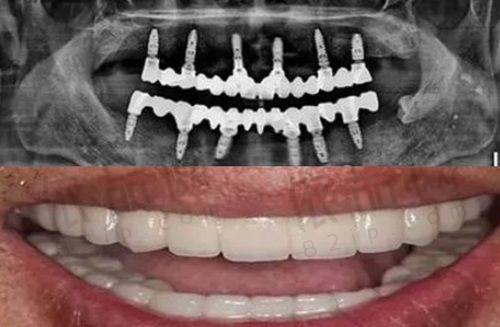

一家正规的口腔机构,精良的技术和设备是必不可少的。哈尔滨美植口腔以种植牙为核心优势,采用数字化种植技术。这种技术结合了3D口腔CT、全景摄影仪等精良设备,能够高精规划种植体的角度和深度。通过这些高新科技设备的辅助,医生可以更精细地了解患者口腔内部的情况,从而降低手术风险。在“即刻种植”“复杂种植”领域,哈尔滨美植口腔表现突出,众多患者反馈种植牙术后成效稳定,使用寿命较长。这说明该机构在种植牙技术方面有着较高的水平和丰富的经验。